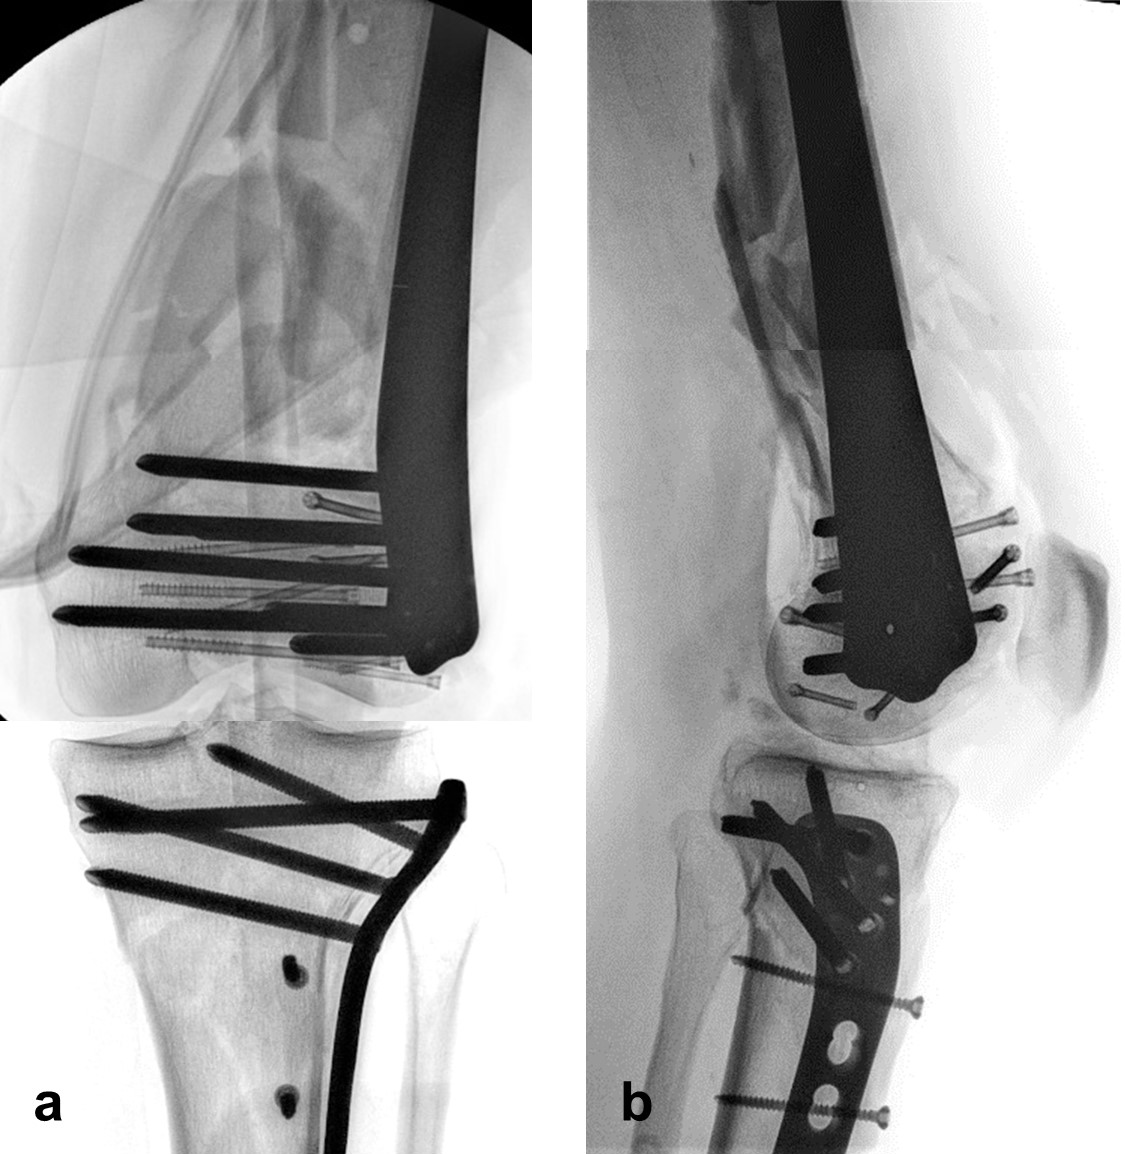

The distal femoral fracture was fixed 3 weeks after injury with ORIF and a Biphasic Plate DF (Fig 6).